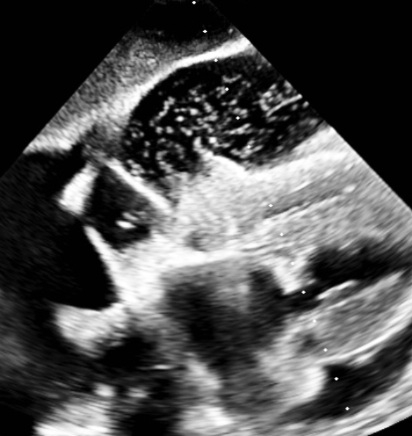

Microbubbles In the Pericardial Space: An Unusual Echocardiographic Finding

Hydropneumopericardium is a term used to describe accumulation of fluid as well as air in the pericardial space. Air or microbubbles in the pericardial space are rare findings typically associated with trauma, invasive procedures, or mechanical ventilation. Less common causes include malignancy, infection, and spontaneous erosion of adjacent structures. Early identification is important, as pneumopericardium can lead to tamponade and have a high mortality rate.

A 79-year-old woman with asthma presented with dyspnea, orthopnea, weight loss, and a right chest wall mass for 7 years. CT image revealed bilateral pleural effusions, a large pericardial effusion, and a right upper lobe soft tissue mass. Transthoracic echocardiography revealed a large pericardial effusion with unusual bright echo densities suggestive of microbubbles, raising concern for potential pneumopericardium. Pericardiocentesis was performed, yielding 400 mL of serous fluid. The drain remained in the place for approximately a week with persistent drainage that tapered slowly. The patient opted against getting a prophylactic pericardial window. Cytology reports came back positive for malignant effusion with suspected primary as malignant breast cancer, that is Estrogen Receptor and Progesterone Receptor positive. She was then started on Anastrozole and discharged to rehab with close follow up with oncology.

Pneumopericardium is most often related to trauma, barotrauma, or procedures such as pericardiocentesis, pacemaker placement, or esophagectomy. Less common causes include malignancy, tuberculosis, aspergillosis, and gastropericardial fistulae. Microbubbles in the pericardial space may be an early sign of air leakage, often preceding overt pneumopericardium. In our case, no communication with airways or gastrointestinal tract was identified on imaging, and no mechanical ventilation was used, ruling out barotrauma or fistulization. The presence of microbubbles may reflect localized necrosis or vascular invasion by tumor, leading to micro-air leak. Given the high mortality of unrecognized pneumopericardium and its potential for tamponade, early recognition of intrapericardial bubbles is critical. This case expands the differential diagnosis of this rare echocardiographic finding and highlights the importance of malignancy as an underlying etiology.